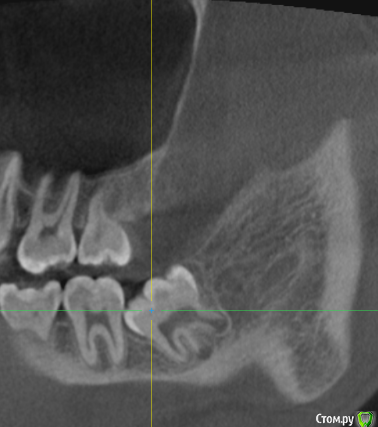

___49___ Опубликовано 12 ноября, 2020 Поделиться Опубликовано 12 ноября, 2020 (изменено) Немного выше в теме скидывал возможные анатомические вариации нижней челюсти , при которых во время удаления 8ки проталкивают апекс язычно .Встречается не часто (реже перфорации верхнечелюстной пазухи ) , но ситуация на мой взгляд менее приятная нежели перфа. Ниже фото пациента , которого я увидел спустя 5 дней после подобного неудачного удаления. Тризм на 1 палец, пациент принимает уже второй курс антибиотиков, t -37-38 , глотание болезненно , флюктуирующего инфильтрата не определяется , кожа в складку собирается, гнойного отделяемого из лунки нет. С молитвами , под торусальной + инфильтрационной анестезией , доступом через внутри ротовой разрез , через минут 10 не активного ( так как тризм , крупный язык ) поиска , удалось поймать "беглеца" , экссудат серозного характера, из лунки удален 2ой апекс, кюретаж, промыта р-ром метронидазола , в лунку введен альванес гель, от дренажа отказался ( при попытке установить , после функциональной пробы - попросил несколько раз открыть и закрыть рот , сглотнуть слюну, дренаж попытался скрыться в глубине мягких тканей) , рану также промыл р-ром метронидазола. Пациент продолжил прием ранее назначенных ему антибиотиков. Осмотры на 2 ой и 4 ый день , динамика положительная. По прошествии 2 недель , открывание рта в полном объеме , t в норме....апексы пациент забрал на память ) . Изменено 12 ноября, 2020 пользователем ___49___ 11 Ссылка на комментарий